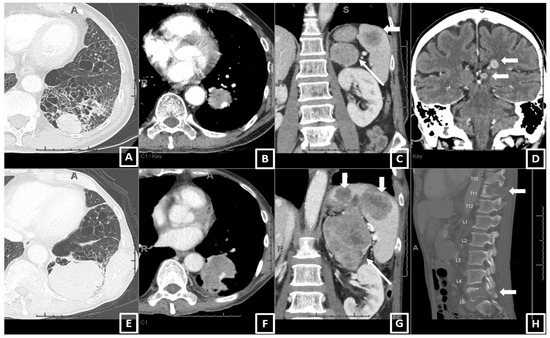

2.2. CT Scan Acquisition and Review

| On baseline CT: Number of patients with metastatic involvement in organs (n, col%) | |||||||

| Lung | 72 | 52.17 | 27 | 58.70 | 45 | 48.91 | 0.3662 |

| Lymph node | 114 | 82.61 | 42 | 91.30 | 72 | 78.26 | 0.0612 |

| Adrenal | 33 | 23.91 | 16 | 34.78 | 17 | 18.48 | 0.0554 |

| Liver | 16 | 11.59 | 10 | 21.74 | 6 | 6.52 | 0.0119 * |

| Bone | 48 | 34.78 | 26 | 56.52 | 22 | 23.91 | 0.0003 * |

| Brain 3 | 21 | 15.22 | 7 | 15.22 | 14 | 15.22 | 1.0000 |

| Pleura 4 | 43 | 31.16 | 18 | 39.13 | 25 | 27.17 | 0.1775 |

| On baseline CT: Number of involved organs with metastasis per patient [median, Q1–Q3] | |||||||

| 3 | 2–4 | 3 | 2–4 | 2 | 2–3 | 0.0015 * | |